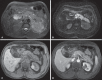

Acute pancreatitis is an inflammatory condition caused by intracellular activation and extravasation of inappropriate proteolytic enzymes determining destruction of pancreatic parenchyma and peripancreatic tissues. This is a fairly common clinical condition with two main presentations, namely, endematous pancreatitis - a less severe presentation -, and necrotizing pancreatitis - the most severe presentation that affects a significant part of patients. The radiological evaluation, particularly by computed tomography, plays a fundamental role in the definition of the management of severe cases, especially regarding the characterization of local complications with implications in the prognosis and in the definition of the therapeutic approach. New concepts include the subdivision of necrotizing pancreatitis into the following presentations: pancreatic parenchymal necrosis with concomitant peripancreatic tissue necrosis, and necrosis restricted to peripancreatic tissues. Moreover, there was a systematization of the terms acute peripancreatic fluid collection, pseudocyst, post-necrotic pancreatic/peripancreatic fluid collections and walled-off pancreatic necrosis. The knowledge about such terms is extremely relevant to standardize the terminology utilized by specialists involved in the diagnosis and treatment of these patients.